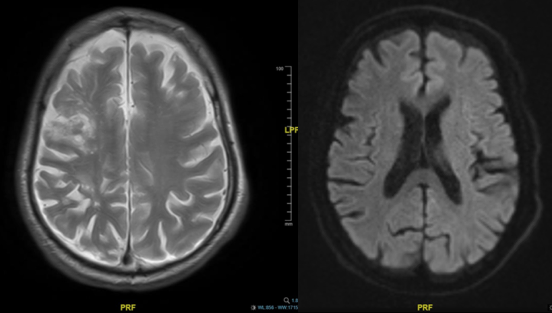

图1 MR提示存在陈旧性脑梗死,无新发梗死